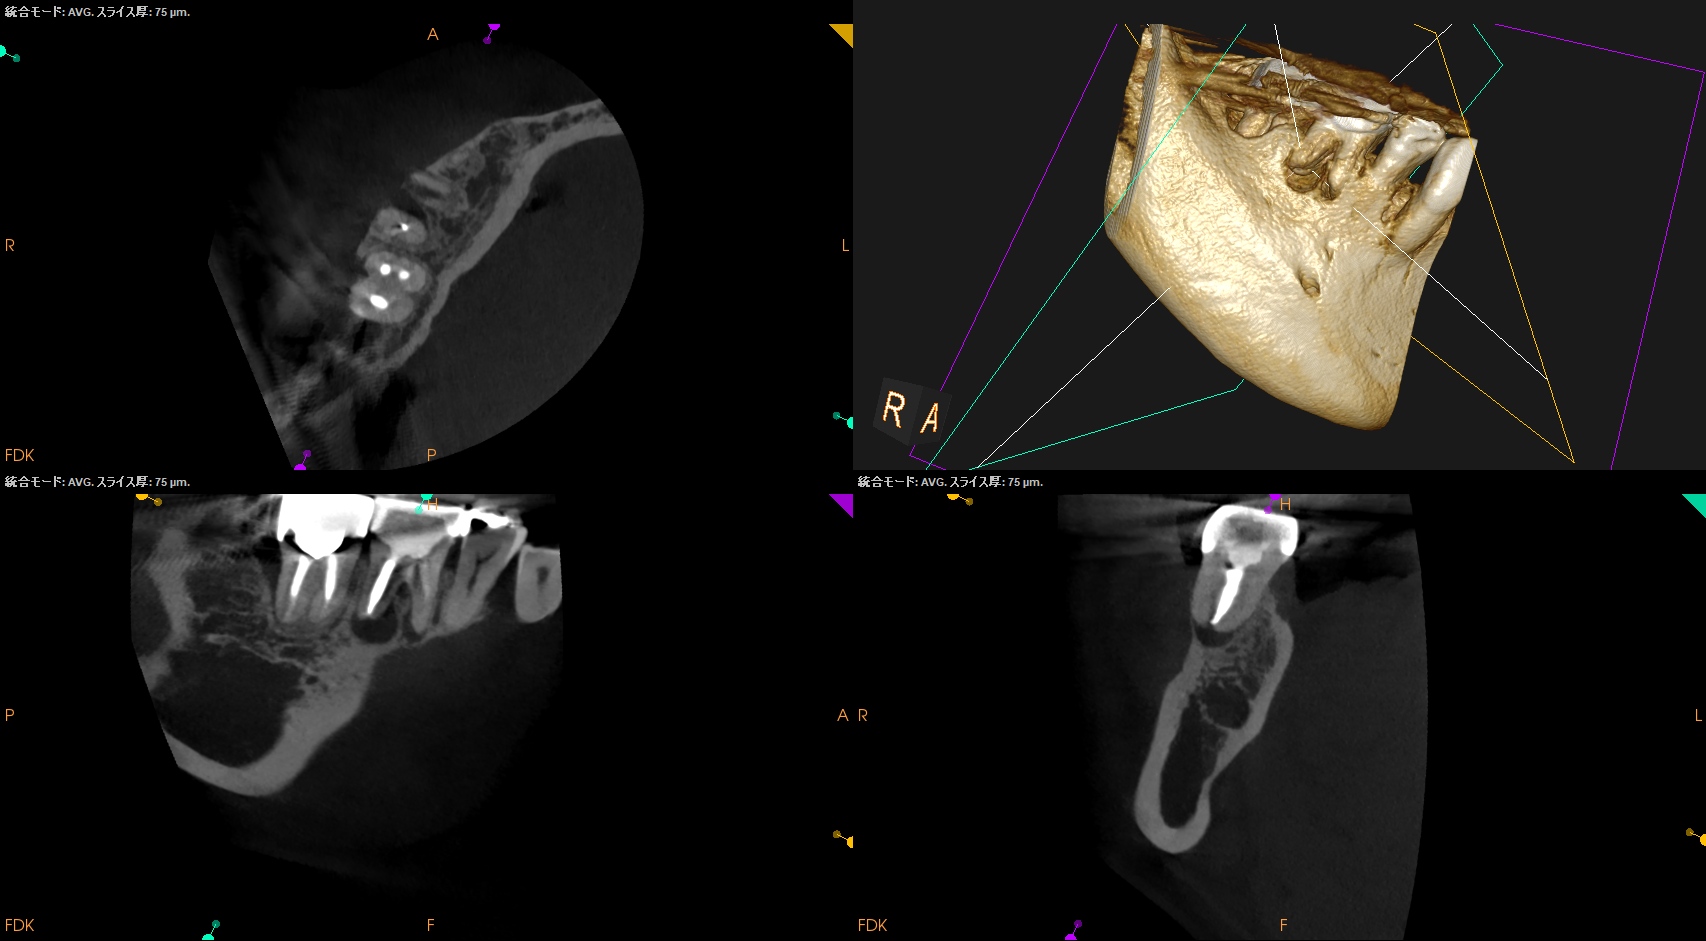

CBCT(2025.9.16)

#30

MB

ML

D

B

頬側の皮質骨が裂開していることが圧痛の原因だろう。

が、Suns tractがないのでApicoectomy!というよりは再根管治療だろう。

ということで、別日に再根管治療へ移行することになった。

その際は、

この絵を参考に行うことができるだろう。